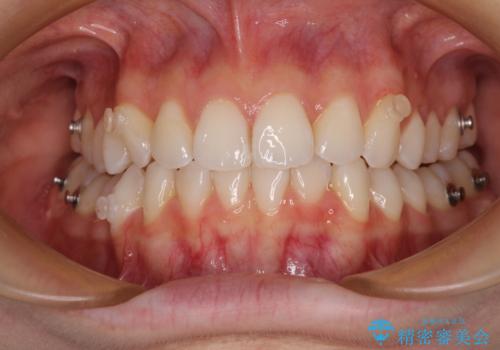

- 矯正装置

- インビザライン

インビザラインは、装着していない時間がどれだけ短いかが、治療期間を大きく左右します。こちらの患者様は1日22時間以上、毎日欠かさず装着してくださったため、1年弱という短期間で満足のいく歯列に整えることができました。